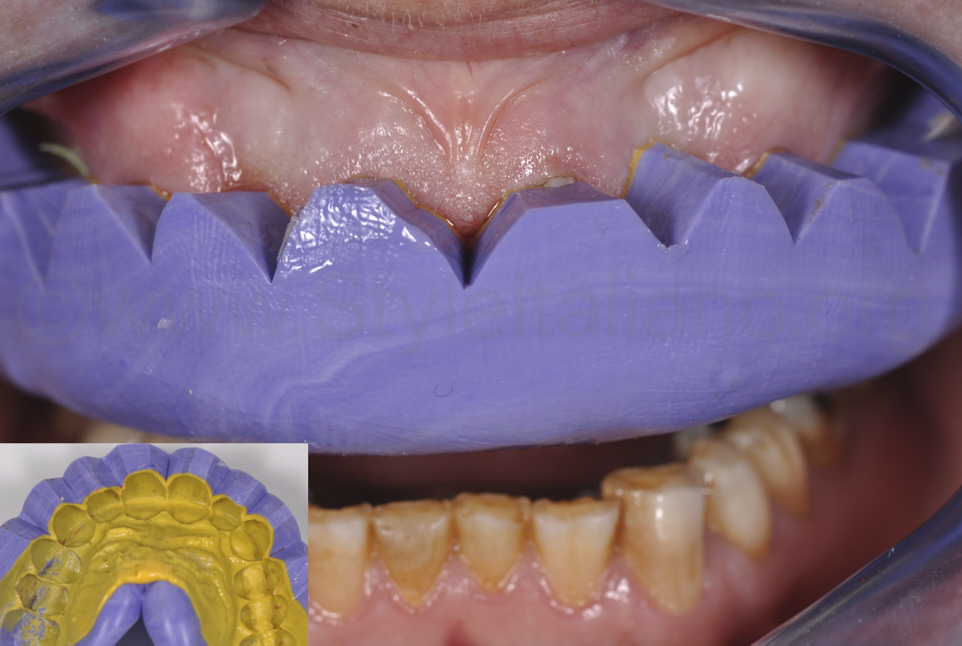

Фото 7.

Щоб швидко виготовити тимчасові конструкції, за естетичним wax-up було виготовлено силіконовий ключ (Honigum Putty Soft і Homigum Light, DMG, м. Гамбург). Цей ключ було підрізано у пришийковій зоні, щоб можна було легко помітити та видалити зайвий композит і виготовити тимчасову конструкцію протягом 5 хвилин.